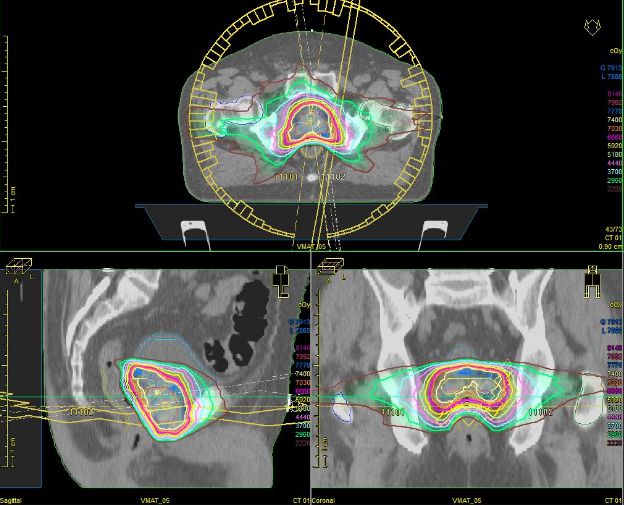

(2)三维适形放疗(3D-CRT)和调强适形放疗(IMRT):三维适形放疗和调强适形放疗可增加前列腺患者肿瘤局部的照射剂量及靶区的照射总量,提高前列腺癌患者局部控制率和无病生存率,同时能最大限度地降低对周围正常组织器官如直肠、膀胱等照射剂量,降低并发症。目前,3D-CRT 及IMRT是前列腺癌放射治疗的最主流技术,临床已经广泛应用。

①照射范围的界定:应用螺旋CT薄层扫描,绘出靶区及正常组织的几何模型并建立数字重建图,经CT模拟机模拟,由医师进行3D放射剂量分析,使外照射的剂量达到很高的适形程度,靶区边缘也可达到标准照射剂量。T1a期前列腺癌患者只需照射前列腺区而不需包括精囊,而T1b~3期患者照射靶体积应包括前列腺、精囊及周围25px范围内的组织。

②照射剂量:3D-CRT和IMRT技术的照射剂量可最高达81~86.4Gy,对直肠及膀胱的副作用无明显增加。

③剂量分割方式:分割照射剂量可以采用常规分割照射,即每日照射剂量1.8~2.0Gy,每周5次,每天照射四野;或采用高剂量分割照射,每日照射剂量2.5~3Gy/次。总照射剂量根据临床分期和预后因素决定,一般总量为70~80Gy,局部晚期前列腺癌应给予较高的照射剂量。如果做全盆腔照射,照射剂量为45~50Gy/5周,然后缩野照射前列腺,补量25~30Gy。局限性前列腺癌应用3D-CRT或IMRT照射时,提高分次照射剂量可缩短疗程,取得与常规分割照射同样的疗效,而正常组织远期并发症未增加。